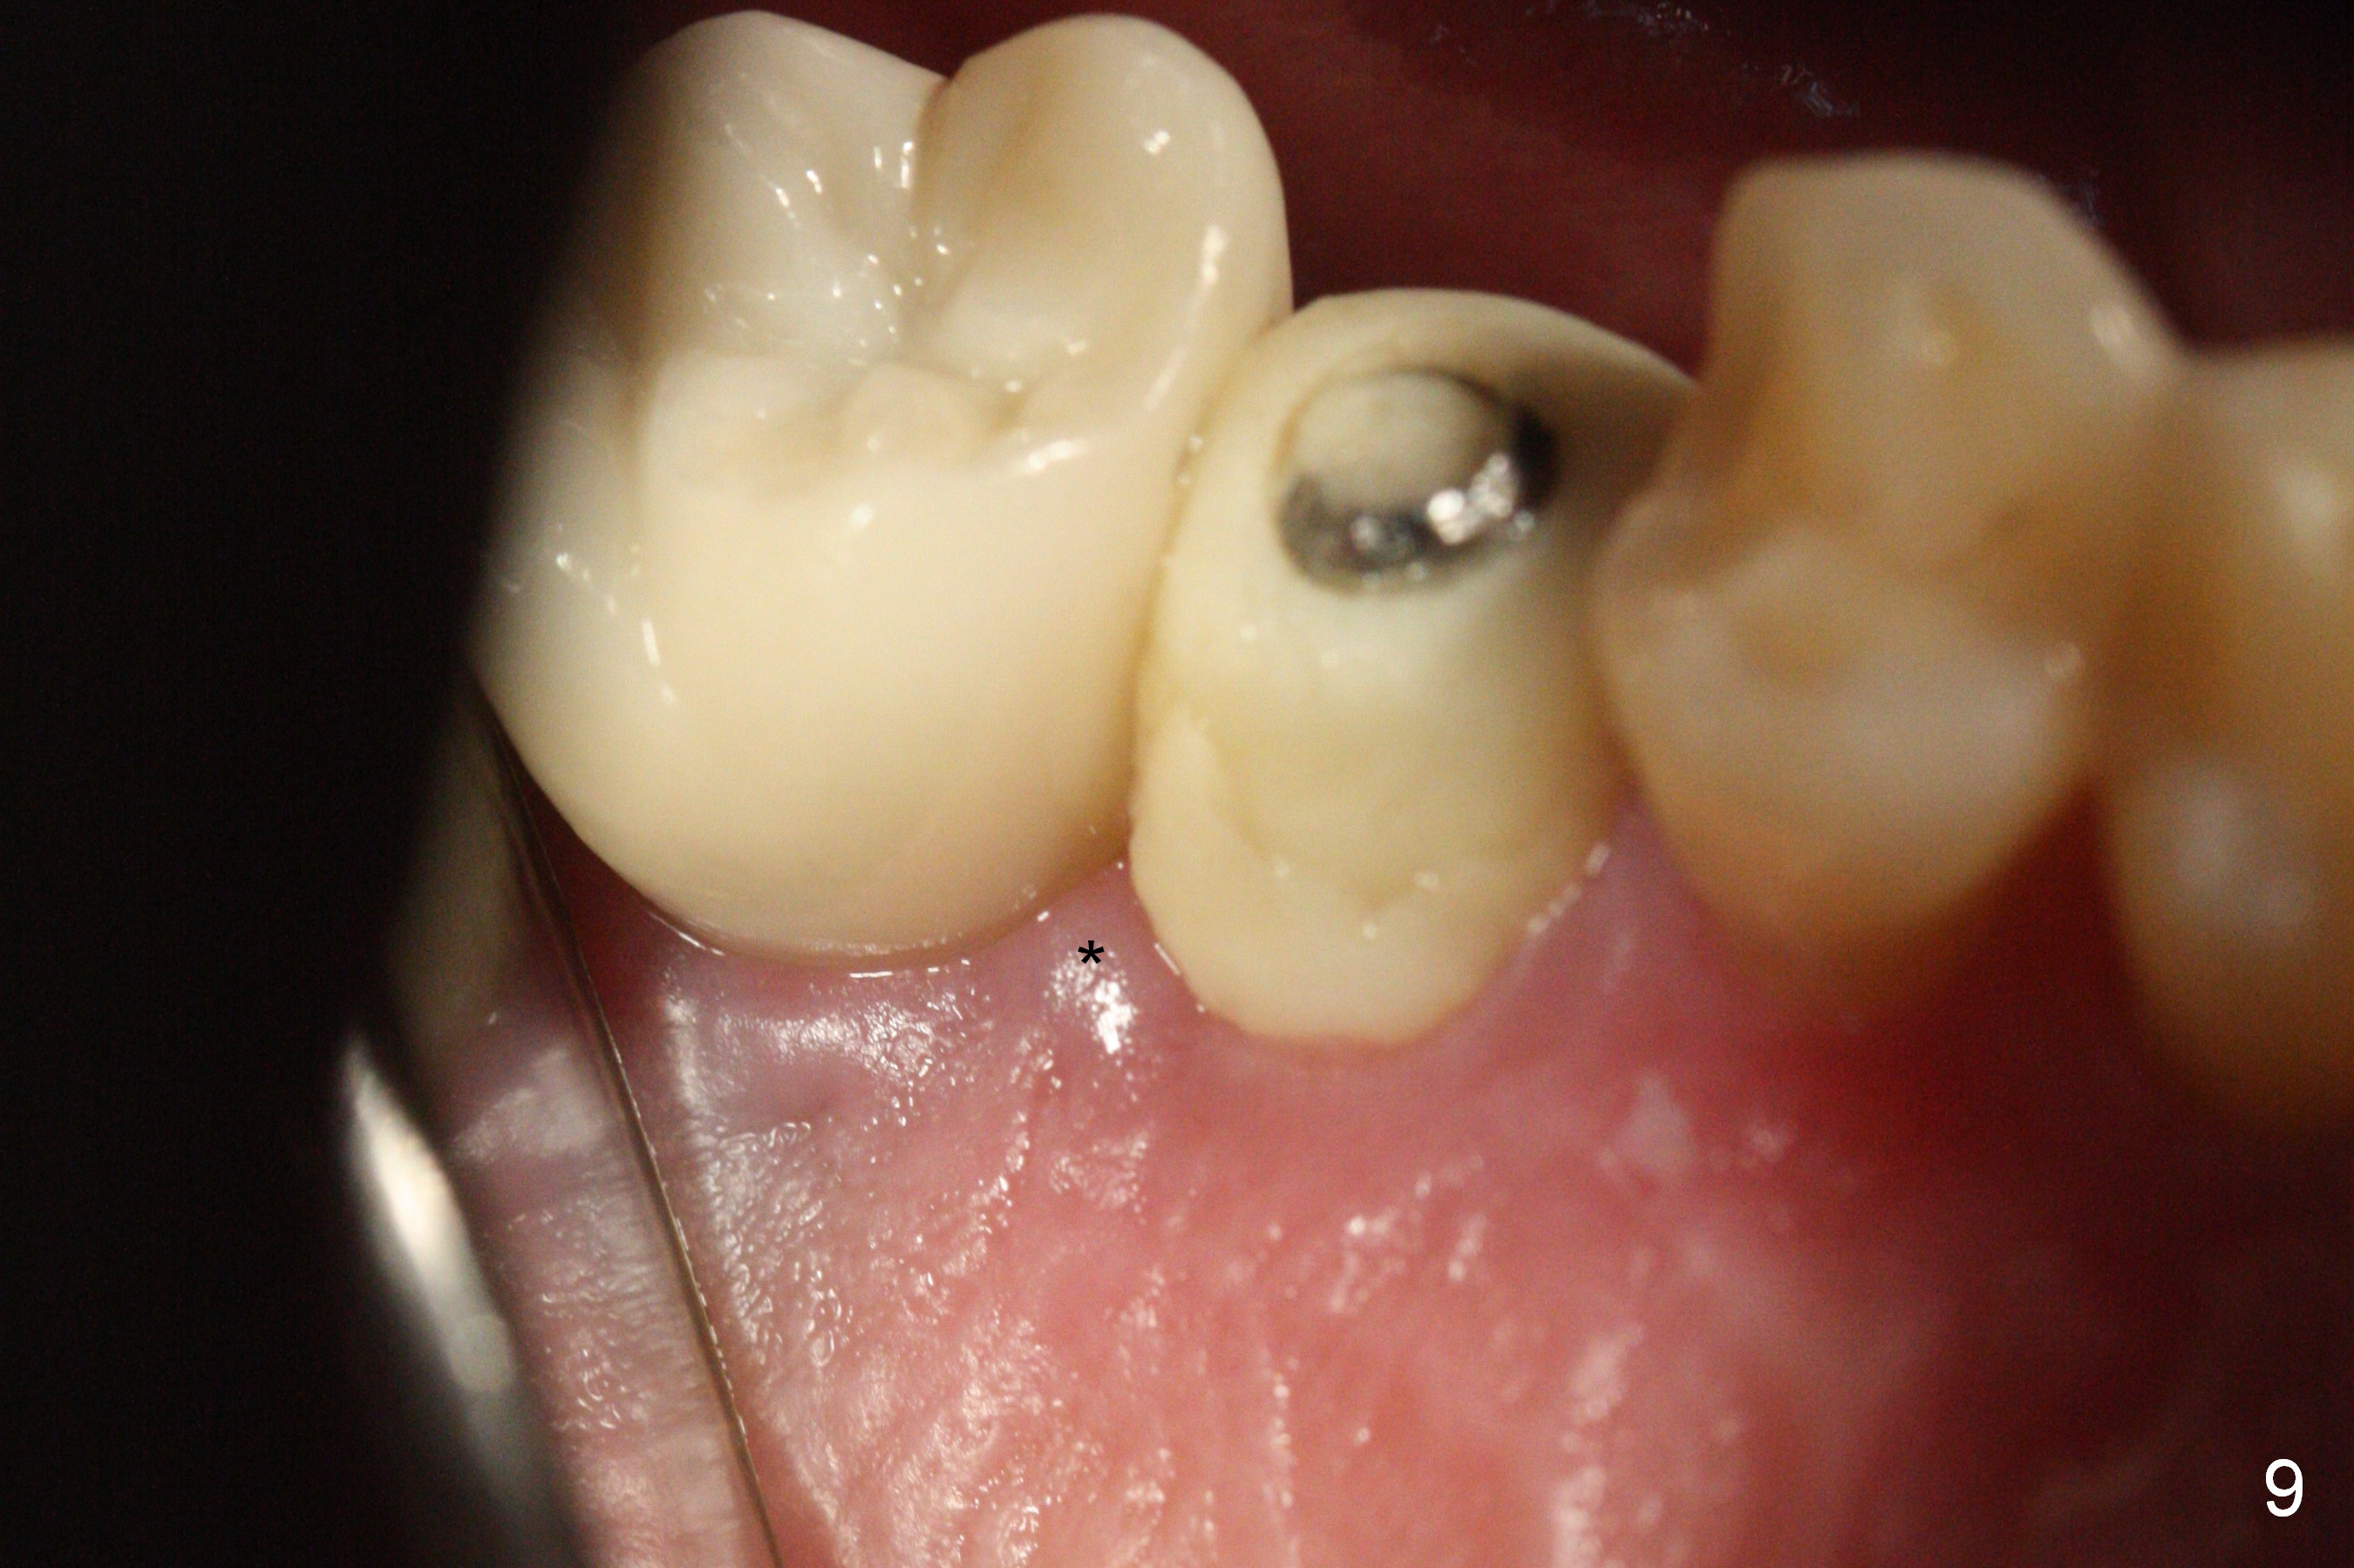

The distal papilla reforms buccally (Fig.8 *) and palatally (Fig.9) 4 months postop. It appears that the 4 mm cuff of the pair abutment (Fig.10 >) is apical to the mesial crest (*). The distal coronal implant threads seem to be covered by bone graft (Fig.11 <). Therefore pair abutments with 5 mm or more cuff are required in cases of the uneven bone. Implants have to be placed deep. CT taken 3 months post cementation (10 months postop) shows that the implant is placed in the middle of the alveolus without apparent thread exposure. CT taken 1 year and 8 months post cementation (Fig.13) shows that the implant is placed in the middle of the alveolus without apparent thread exposure, as compared to those at #2 and 3, which are placed buccal (B).